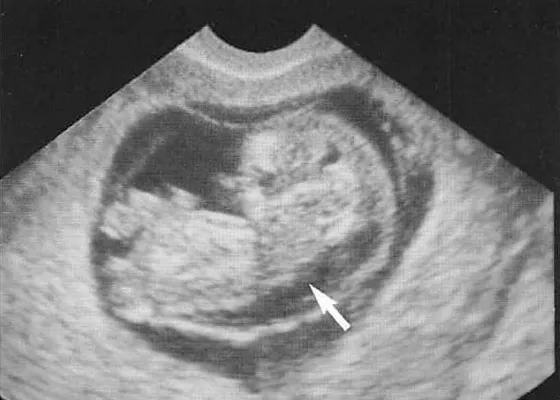

20代18トリソミー|健診で先生がNT肥厚と書いたのに説明してくれない

NIPTの後に赤ちゃんのNT肥厚(首の後ろのむくみ)が指摘